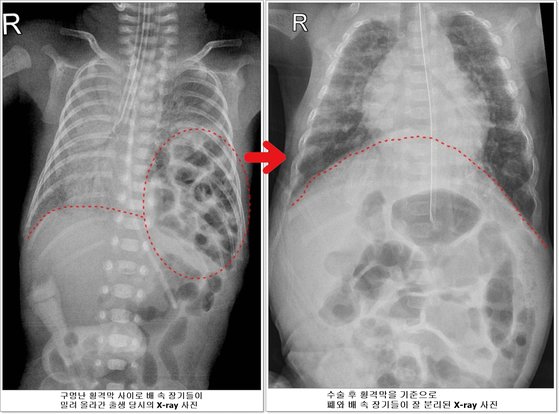

구멍난 횡격막 사이로 배 속 장기들이 밀려 올라간 출생 당시의 X-ray 사진(왼쪽)과 수술 후 횡격막을 기준으로 폐와 배 속 장기들이 잘 분리된 X-ray 사진 [서울아산병원] |

선천성 횡격막 탈장증이란 가슴 안에 심장과 폐를 배 속의 소화기 장기들로부터 분리해주는 횡격막에 선천적으로 구멍이 생기는 질환이다. 배 속의 장기가 횡격막의 구멍을 통해 밀려 올라와 가슴안의 심장과 폐를 압박한다. 이 때문에 폐가 제대로 펴지지 않아 호흡 곤란이 생기고 심장기능도 떨어지게 된다.

고비도 많았다. 아이는 소화기관이 모두 가슴 안으로 올라가 있어 모유도 먹을 수 없는 상태였다. 중심 정맥관을 통해 주사 영양제를 투여했지만 주사 영양제를 해독하기 위해 간의 부담이 커지면서 담즙정체가 일어났고 장폐색이 발생하기도 했다.

하지만 호삼이는 이 모든 위기를 다 이겨내고 태어난 지 40일이 되던 5월 20일에 체중 1530g으로 자랐다. 덕분에 소아외과 남궁정만 교수가 구멍 난 횡격막을 막는 수술을 성공적으로 시행할 수 있었다. 그 후 출생 47일째 인공호흡기를 빼고 스스로 숨을 쉬기 시작했고, 입으로 모유를 먹을 수 있을 정도로 빠르게 회복되면서 체중 2.4kg이 되어 지난 25일 집으로 돌아갈 수 있게 됐다.